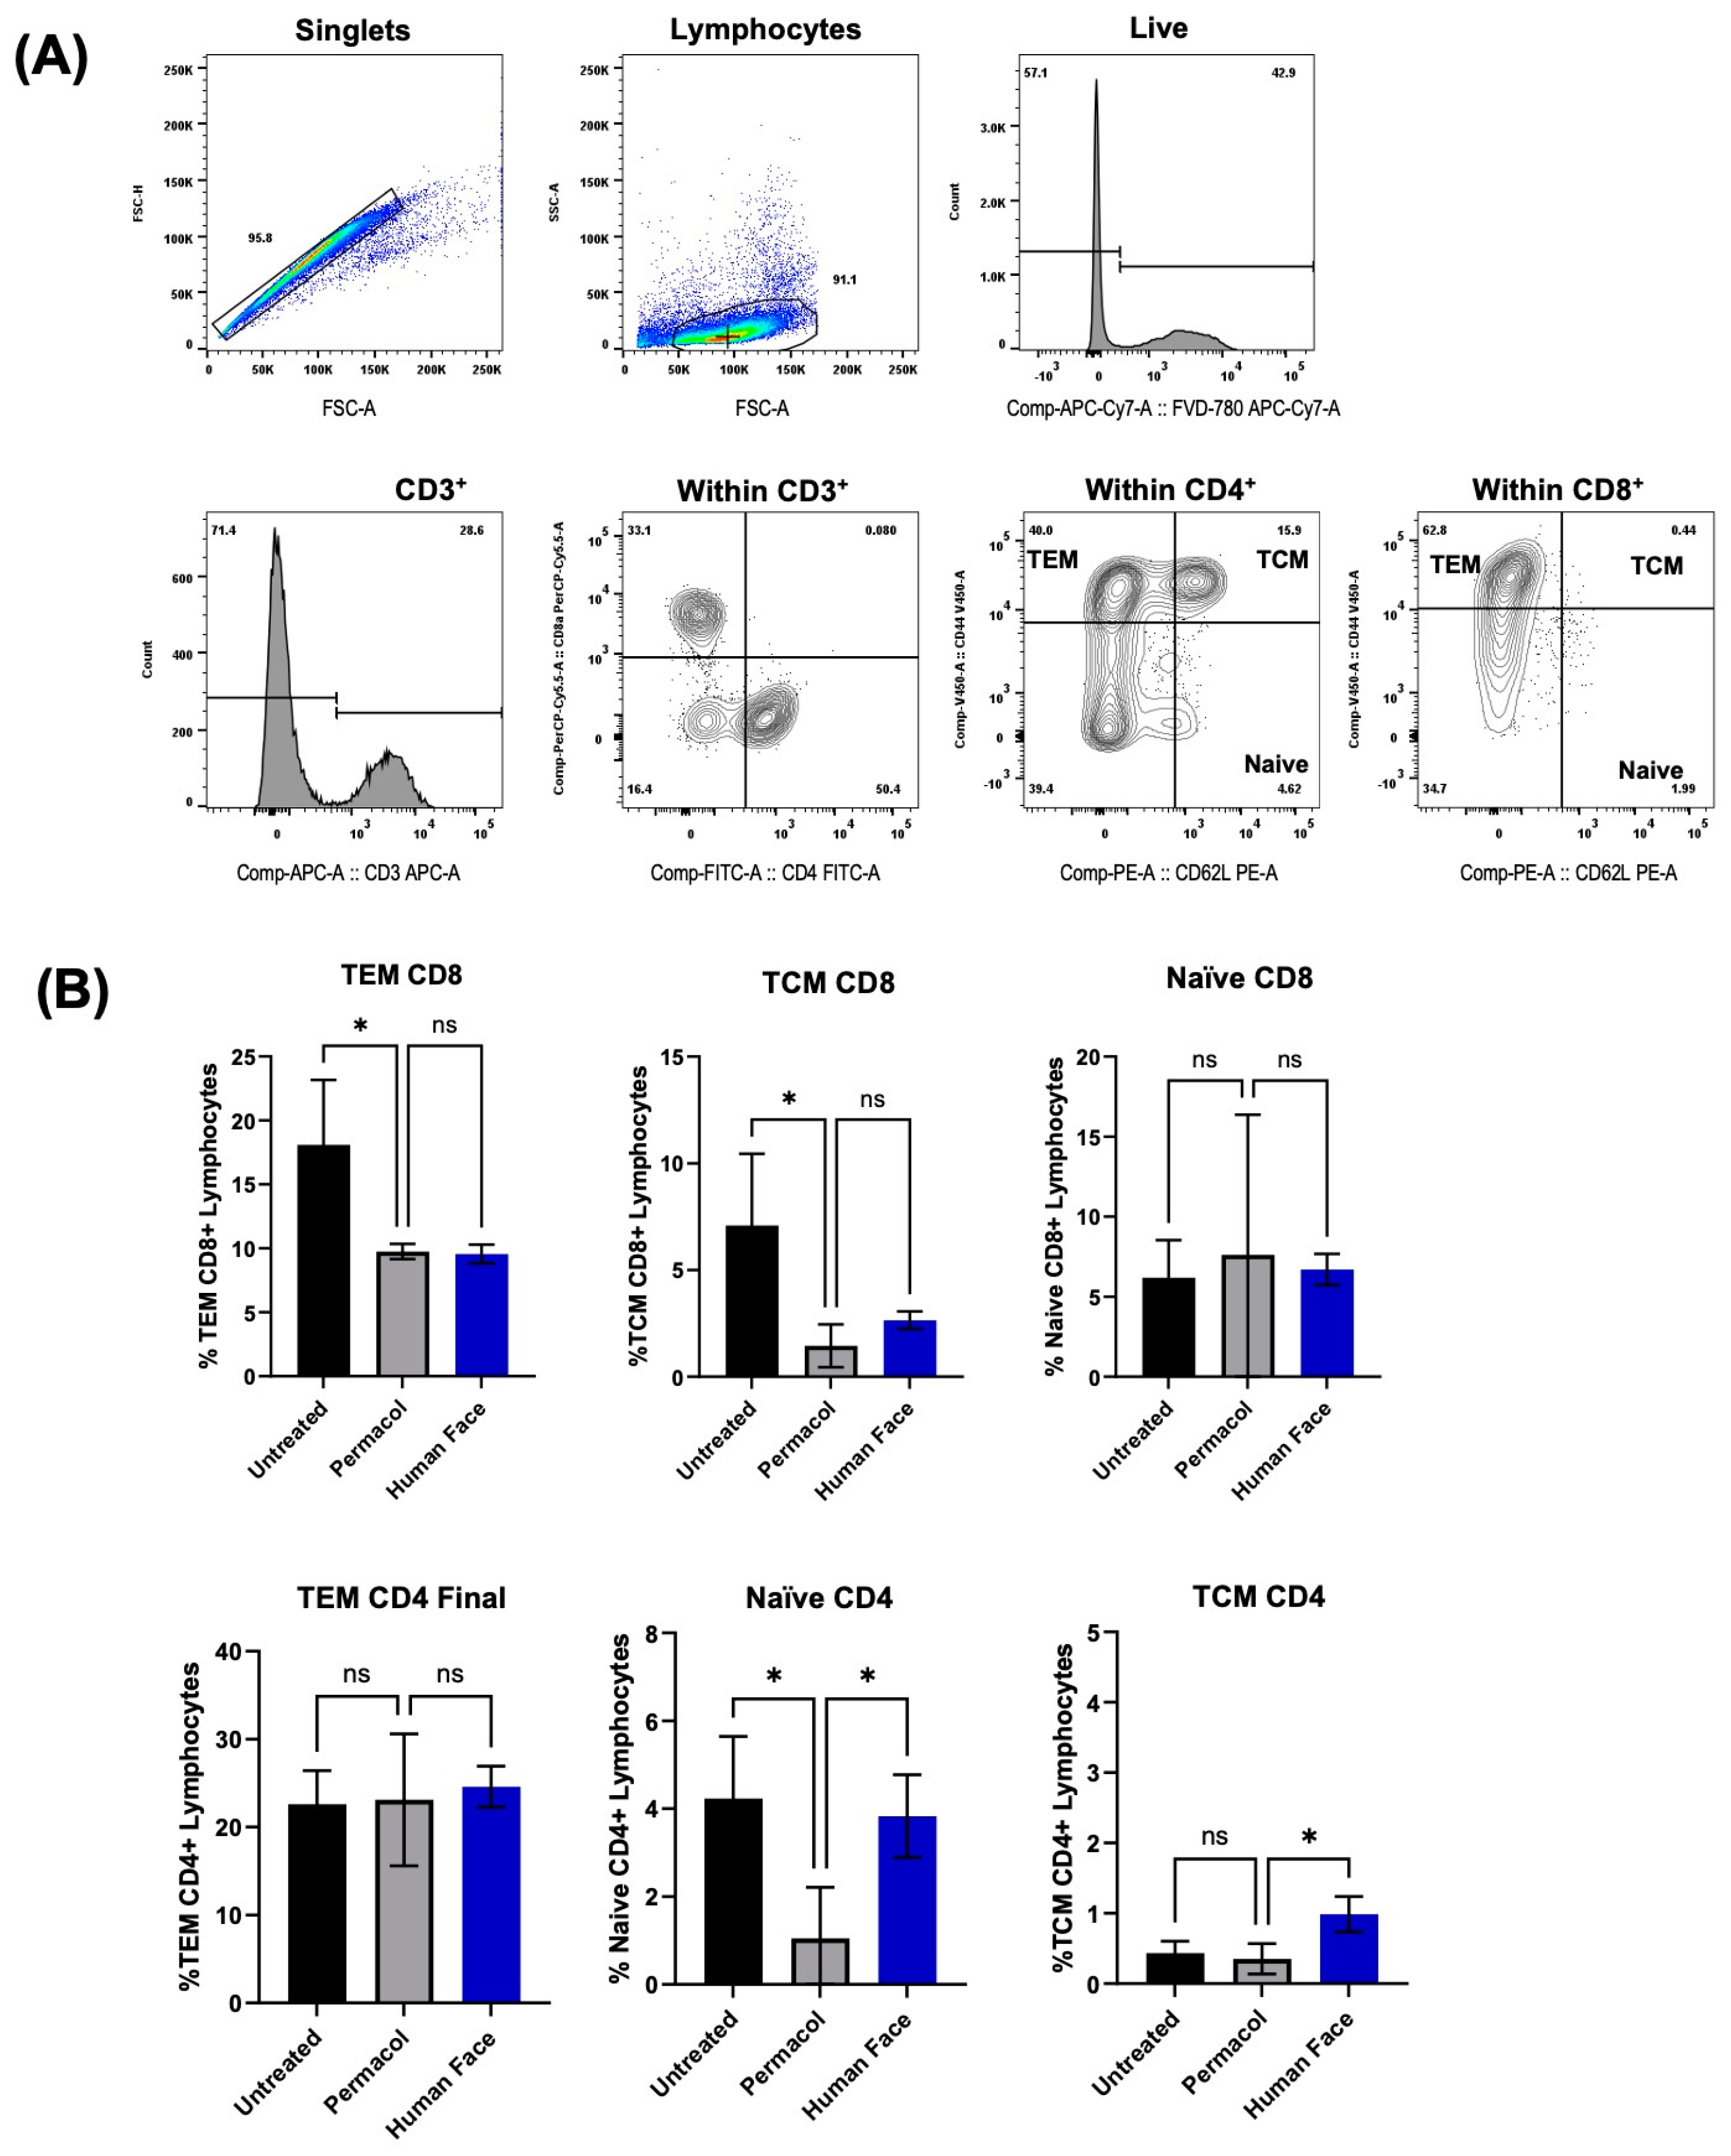

3.4. In Vitro and In Vivo Biocompatibility of Decellularized Facial Grafts